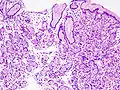

Гиперпластический полип